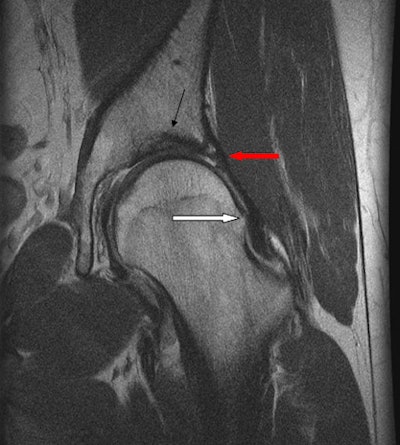

In my practice, we see a large amount of knee injuries (meniscal, cruciate, and medial collateral ligament) -- ankle injuries, predominantly ligaments, shoulders (dislocations with sequelae of same), hand injuries (particularly fractures in hurling and ulnar collateral ligament injuries), and groin pain (osteitis pubis, adductor/gracilis/rectus abdominis injuries, labral tears).

MRI is our test of choice for nearly all sports injuries, apart from obvious fractures and hand injuries. All knee, shoulder, hip, groin, and muscle injuries are evaluated with MRI. Shoulder and hip MR arthrography are reserved for those who have indeterminate noncontrast MRI for evaluation of labral and cartilage injuries or who have a high level of suspicion for these injuries from the outset. Ultrasound is often the first test for tendon injuries, such as Achilles, peroneal, and wrist tendons, with MRI reserved for more detailed analysis as necessary.